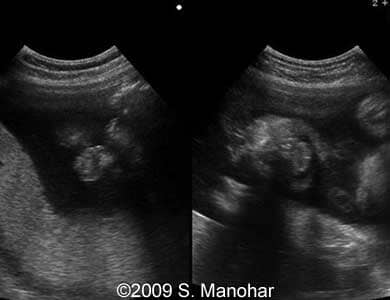

Images 1, 2: The images show an edema of the fetal eyelid"s ectropion (arrows).

1

6